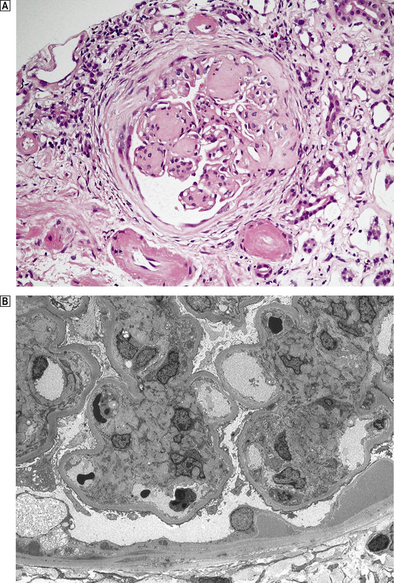

Histologically, the characteristic lesion is a focal and segmental glomerulonephritis. With increasing severity, segmental necrosis with fibrin deposition, and a florid crescentic glomerulonephritis occurs (Fig. 21.5).

image

Fig. 21.5 Anti-glomerular basement membrane disease. The glomerular injury in this case is due to anti-glomerular basement membrane antibody. image The resulting damage causes obliteration of the Bowman’s space by macrophages, inflammatory cells and epithelial cells forming a crescent. image Immunofluorescence reveals linear deposition of immunoglobulin on the glomerular basement membrane.